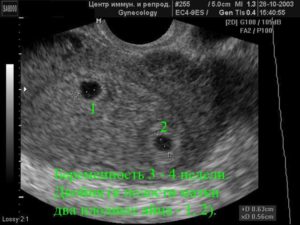

Возникает вопрос: на каком сроке УЗИ покажет беременность и есть ли смысл на 1-2 неделе задержки идти на обследование, чтобы уже окончательно определиться? Ответ – стоит: УЗИ способно показать беременность уже на сроках в 3-4 недели, а это как раз и есть те самые 1-2 недели задержки месячных.

Вот только не всегда, если УЗИ покажет плодное яйцо на самых ранних сроках, можно гарантировано говорить о наличии беременности. К сожалению, плодное яйцо может оказаться пустым и не содержать в себе эмбриона, и установить это будет возможно только с 5 недели беременности.

На раннем сроке с 4 по 6 недели срок беременности устанавливают по диаметру плодного яйца. Для этого врач проводит измерение диаметра плодного яйца по его внутреннему контуру в 3 взаимоперпендикулярных плоскостях.

- 3-я неделя – в это время можно увидеть первый достоверный признак формирования плода, при качественно проведенном исследовании (независимо от его вида – трансабдоминальное или трансвагинальное). На мониторе УЗИ визуализируется начальное изображение плодного яйца, которое начинает формироваться на 15-й день. Оно виден, как эхонегативное образование (участок темного пространства). Форма, как правило, круглая или слегка вытянутая по полюсам. Диаметр на 20-й день составляет от 4-х до 6-ти мм;